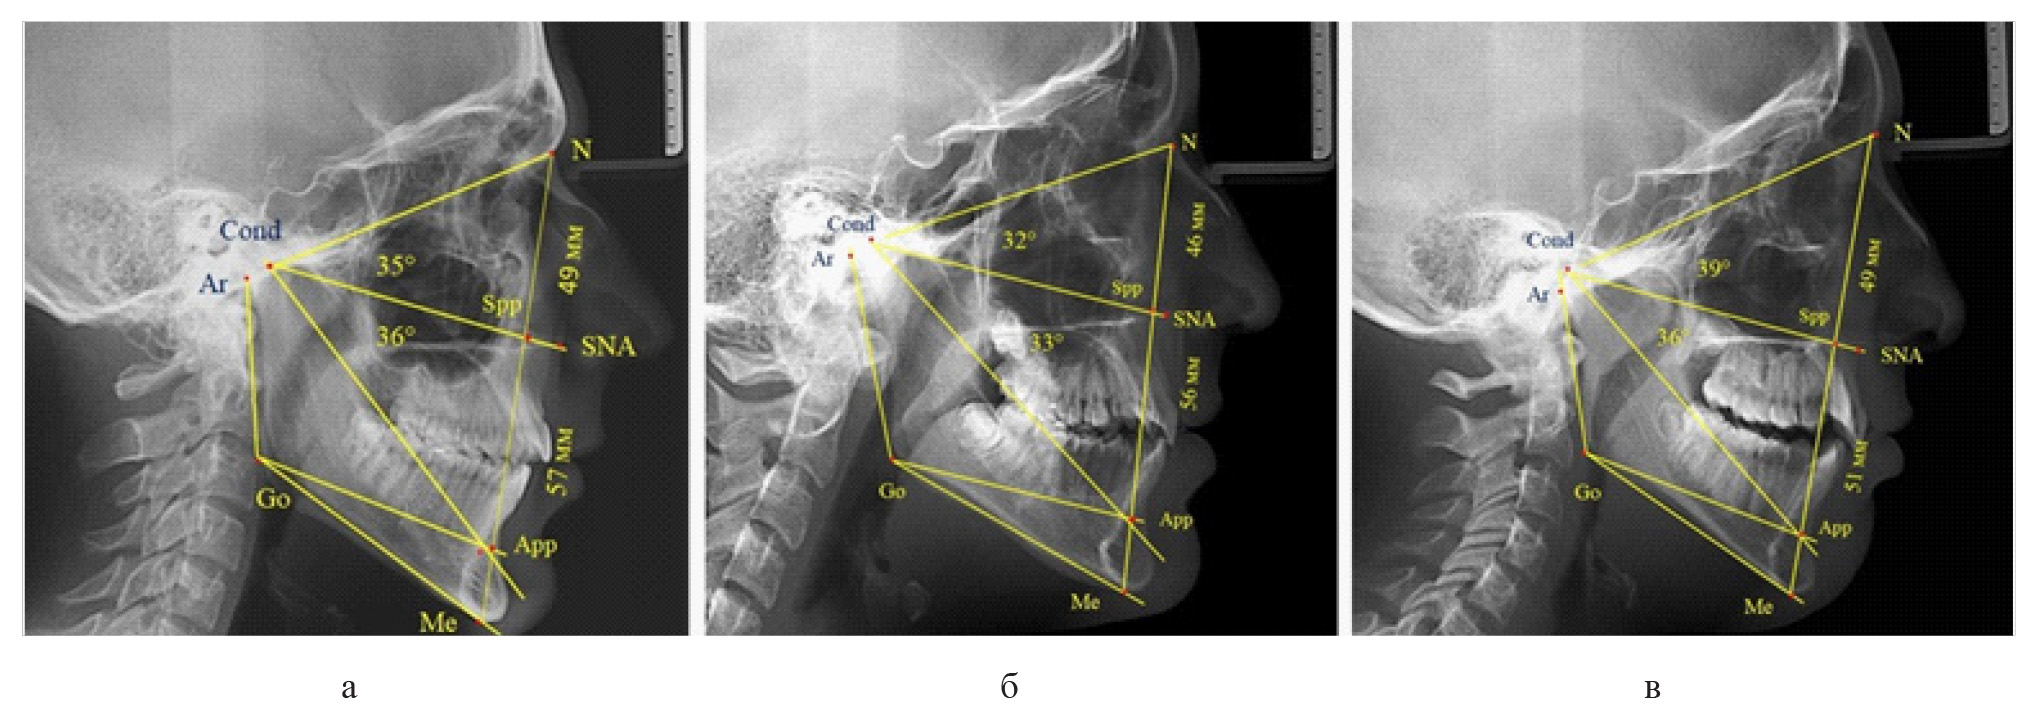

Результаты исследования людей с физиологической окклюзией показали, что у 46 человек [(82,14 ± 5,11) %], параметры назального отдела лица соответствовали оптимальным показателям. При этом у 38 человек [(67,85 ± 6,14) %], определились физиологические показатели параметров гнатической части лица.

У 6 человек [(10,71 ± 4,13) %], отмечалось увеличение параметров гнатической части до уровня физиологического вертикального показателя, а у 2 человек [(3,57 ± 2,48) %], незначительное снижение гнатической части (рис. 3).

Рис. 3. Сравнительный анализ ТРГ с оптимальными размерами носового отдела и оптимальными (а), укороченными физиологическими (б) и увеличенными физиологическими (в) размерами гнатической части лица